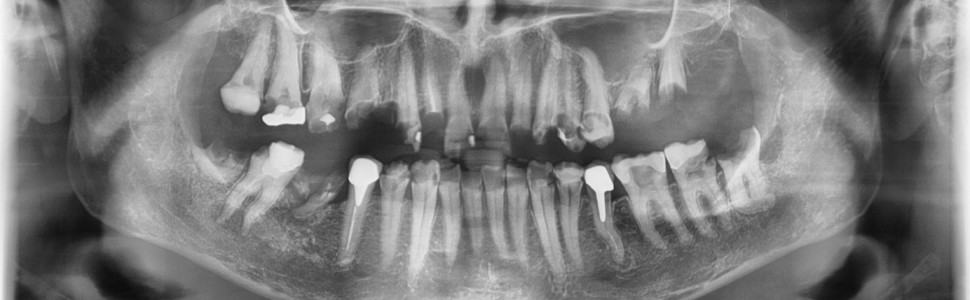

Glejak włókienkowy to nowotwór złośliwy OUN II stopnia złośliwości według klasyfikacji WHO. Metodą z wyboru lub uzupełnieniem leczenia jest radioterapia guza mózgu. Opieka stomatologiczna nad pacjentem przed radioterapią głowy i szyi, w trakcie i po jej wykonaniu powinna opierać się na współpracy wielospecjalistycznej. Właściwie postępowanie może zniwelować ryzyko wystąpienia odczynów popromiennych i zapewnić sukces leczniczy.

Fibrillary astrocytoma is a malignant tumor of the CNS WHO grade 2. Radiotherapy is a method of choice or an adjuvant therapy in the treatment of brain tumors. Dental care before, during and after radiotherapy should be based on interdisciplinary cooperation. Appropriate measures can reduce occurrence of the side effects of the therapy and lead to therapeutic success